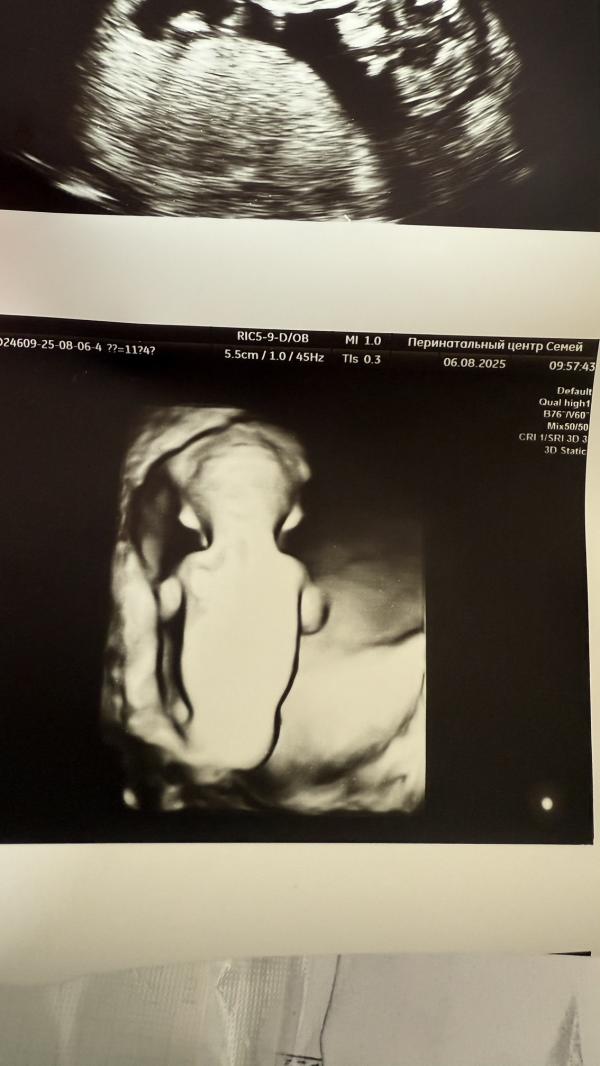

Легкой беременности ! Что за боташка сладкий первый раз вижу так спины мнимок узи 😍

Я тоже таааак удивилась если честно, что в 12 недель таааак четко можно сделать такой снимок😅

И узист такая классная попалась, все показала, вплоть до пальчиков😍

До сих пор под впечатлением🥰